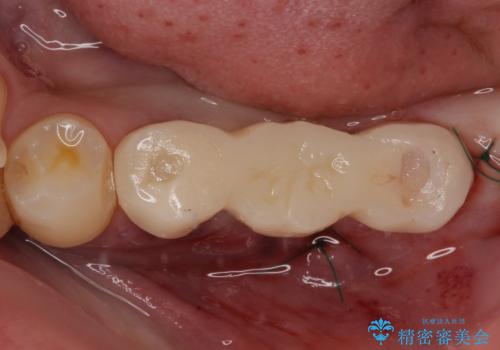

左下小臼歯は根管治療で対応する予定でしたが、診断のために歯肉を開いたところ頬側に垂直破折が認められたため、抜歯即時埋入インプラントによる補綴治療を選択することとしました。

右下は大臼歯部の歯は抜歯即時埋入インプラントにて、手前の歯は保存して補綴治療を行うこととしました。

インプラント埋入時に十分な安定値を得ることができたため、速やかに仮歯を装着し、最小限の通院回数で治療を終えることができました。